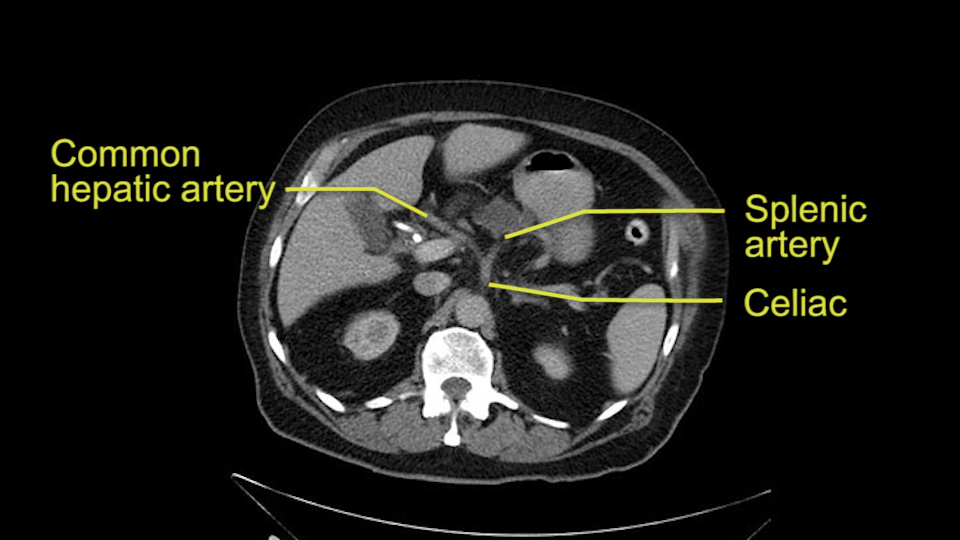

Then you look for anomalies. The one you worry about the most doing a Whipple is a replaced or aberrant right hepatic artery coming off the SMA at its origin. So again, find the SMA. You can find it because the renal vein goes through it. Follow it up, up-up-up. Nothing coming off of there that I can see here. Nothing coming off of it, nothing coming off of it and just to confirm it, look at the celiac trfurcation. There’s the celiac, there’s the bifurcation, there's the splenic artery, hepatic artery. Make sure there’s a right, which there is here. The right usually goes under the bile duct: important when you’re going around the bile duct to do a Whipple. A replaced right goes under the portal vein and the bile duct way over here on the right. That’s about it.